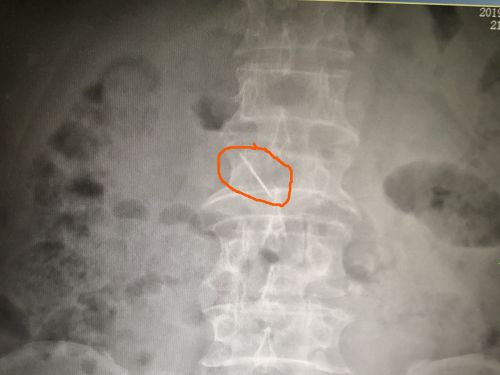

X片显示:老人上腹部有一个细长的高密度异物影。

结直肠肛门外科主任肖志刚教授详细询问病史并进行细致的体格检查后,一时也无法判定病情,于是安排X光检查。结果出来后,所有人都吓了一跳,X线显示:老人上腹部有一个细长的高密度异物影,很可能就是导致他不适的罪魁祸首。